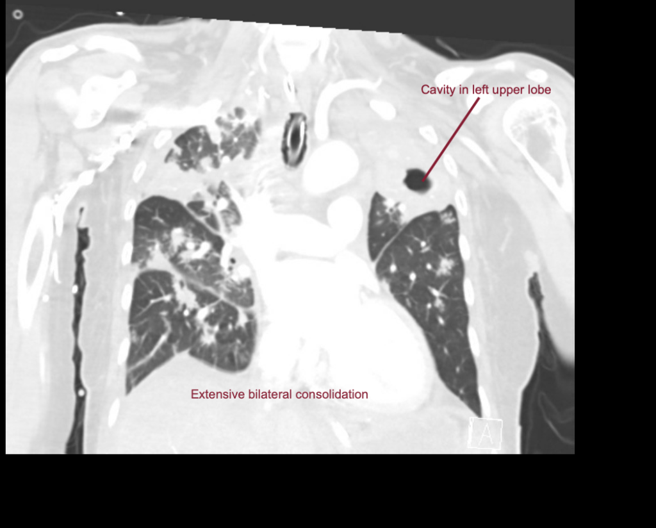

EXPLANATION -There is diffuse bilateral consolidation more prominent in the upper lobes.

There is left upper lobe cavitation. Bilaterally there are pleural effusions.